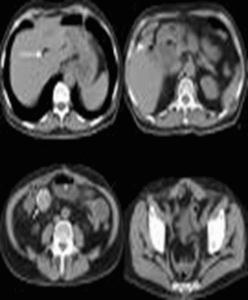

Litiasis Vesicular

CLASSIFICAÇÃO:

ATENDIMENTO COM A NATUREZA DOS CÁLCULOS.

• Cálculos de colesterol.

• Cálculos pigmentares.

• Cálculos mistos.

• Litíase sem perturbações da parede da vesícula biliar: Colelitíase